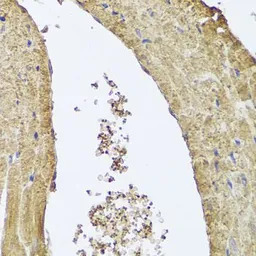

IHC-P analysis of mouse heart tissue using GTX65983 PI3 kinase C2 alpha antibody.

Dilution : 1:100